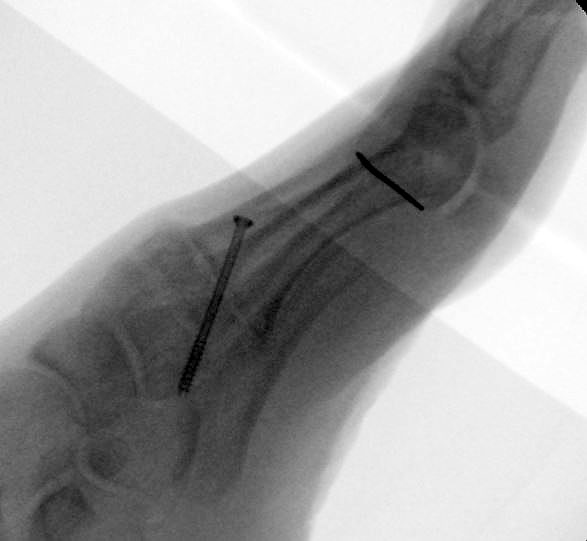

Es wird hier die Lapidusarthrodese mit Fixation durch eine medial angebrachte winkelstabile Platte in Kombination mit einer Zugschraube beschrieben 2. Durch diese Kombination läßt sich eine verglichen zur Schraubenosteosynthese hohe Primärstabilität erreichen, verbunden mit einem niedrigen Risiko einer Pseudarthrosenbildung 3.

Direkt postoperativ Röntgenkontrolle (Fuß in zwei Ebenen). Sechs Wochen postoperative Röntgenverlaufskontrolle in zwei Ebenen im Stehen. Ist die Überbauung der Arthrodese nicht gut zu beurteilen, kann eine ergänzende 45° Supinationsaufnahme des Fußes angefertigt werden, die einen guten Einblick in das Tarsometatarsale-I-Gelenk ermöglicht.